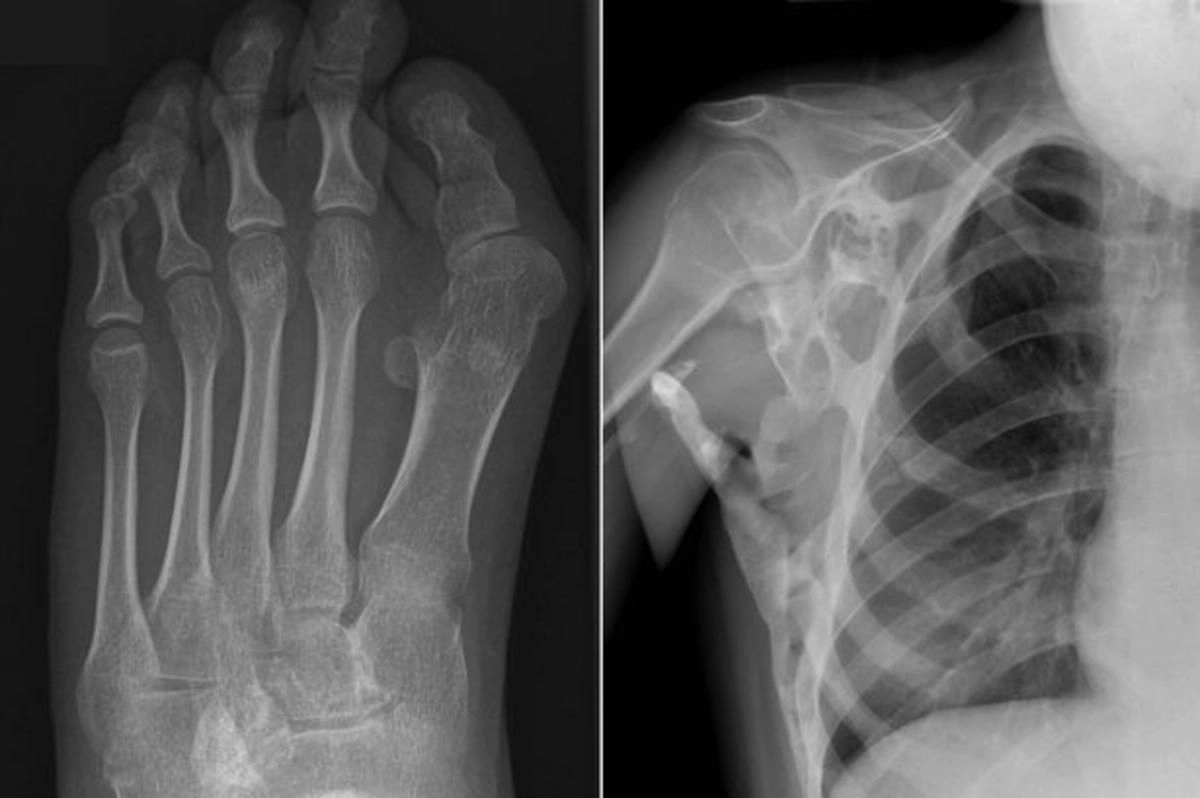

На конференции врачи рассказали, что, несмотря на крайне малую распространенность, заподозрить ФОП несложно: характерным признаком, который встречается у 90% пациентов, заболевания является искривление, укороченность или отсутствие больших пальцев на ногах новорожденного.

У 95% живущих с ФОП большие пальцы ног особым образом искривлены, укорочены и даже могут отсутствовать. Широкая информированность неонатологов об этой особенности позволила бы уже во время первичного визуального осмотра в родильном зале заподозрить эту патологию и направить на генетический анализ. Трудности диагностики ФОП на самых ранних этапах проявления болезни связаны с тем, что большинство врачей не только никогда не видели таких пациентов, но и не имели конкретной информации об этом драматическом страдании, — заявила на пресс-конференции Ирина Петровна Никишина, к. м. н., зав. лабораторией ревматических заболеваний детского возраста с реабилитационной группой ФГБНУ НИИ ревматологии им. В. А. Насоновой.